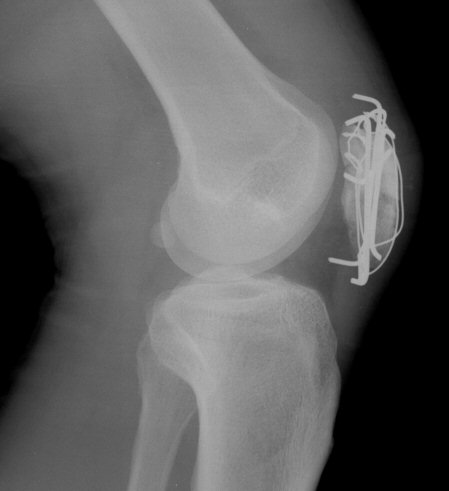

´Ü¼ø¹æ»ç¼±°Ë»ç

½½°³°ñ °ñÀý °íÁ¤ ÀåÄ¡°¡ °üÂûµÊ(»çÁø 6, 7)